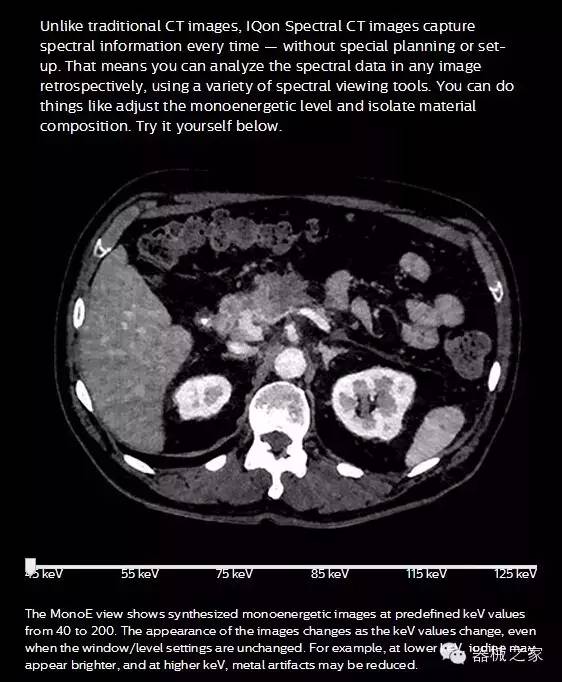

IQon光譜CT -- 是業(yè)界首臺以探測器為成像基礎(chǔ)的光譜CT,它可以在單次常規(guī)掃描下獲得傳統(tǒng)解剖影像及光譜功能影像。不僅可以提供精準(zhǔn)的診斷信息,還可簡化工作流程、在低劑量下完成定量與定性分析。